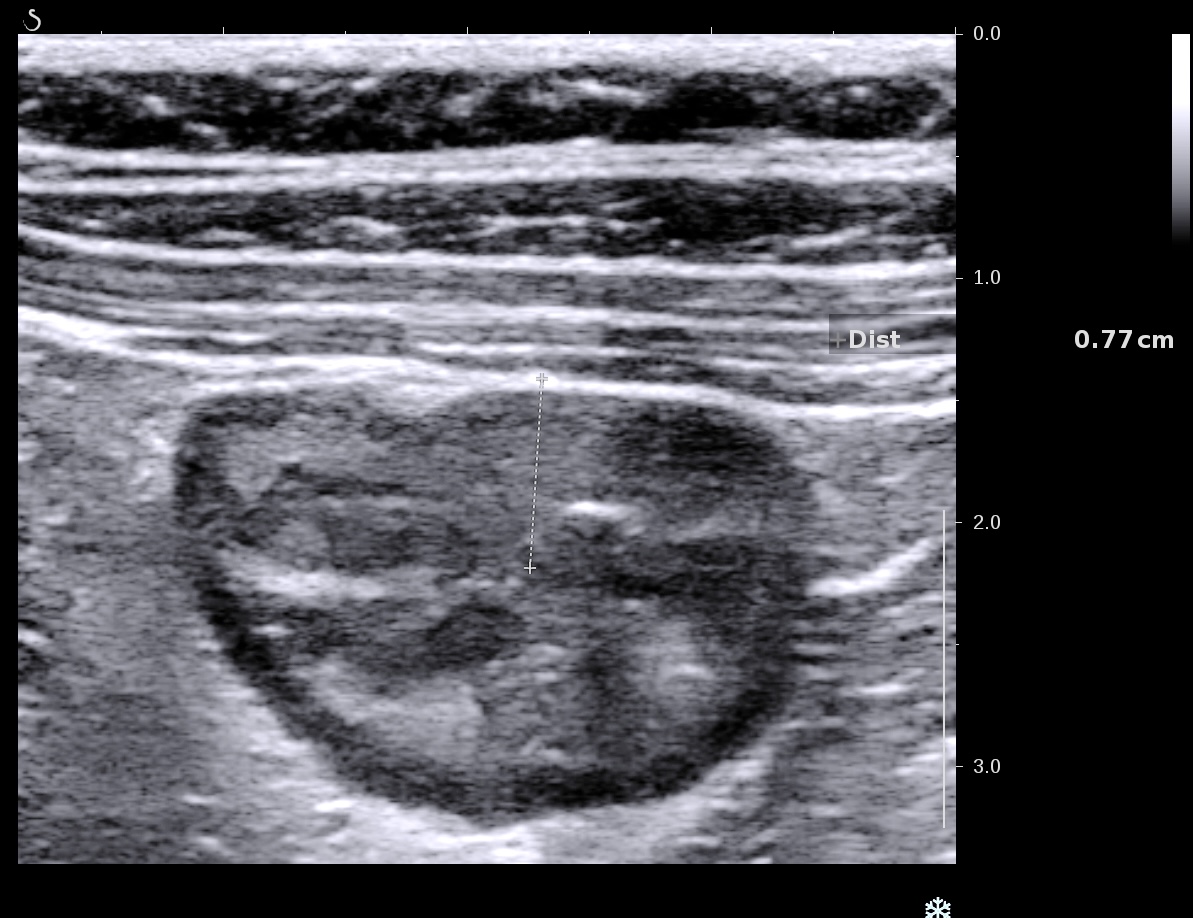

L'épaississement prédomine à la 3 ième couche hyperéchogène( > 1/3 de la paroi), il est continue, régulier, cironférentiel

La structure en couche est conservée

La graisse est peu infiltrée, l'activité doppler modérée.

Muqueuse épaissie en coupe transversale